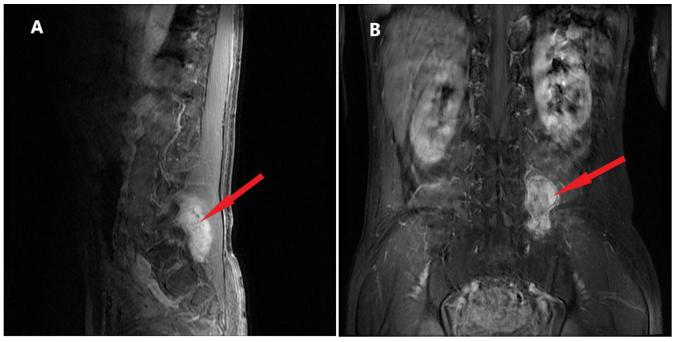

Until recently, few cases of three or more malignant tumors in one patient have been reported. Owing to the high incidence rate of these tumors, the improvement in cancer diagnosis and treatment, and the extension of patient survival time, the incidence of reported multiple primary malignant neoplasms has gradually increased. The present study reported the case of a 57-year-old man with non-small cell lung cancer combined with B-Raf proto-oncogene serine/threonine kinase V600E mutation, gastrointestinal stromal tumors and lumbar vertebral malignant mucinous sarcoma. The pathogenesis, diagnosis and treatment of these three malignancies are discussed and previous studies are also reviewed. The aim of the study was to analyze the genetic mutations associated with multiple primary malignant tumors and to discuss whether those mutations with unknown functional significance could be used as therapeutic indicators. This case report will serve as a reference for future treatment of such patients.

直到最近,关于一名患者患有三种或更多恶性肿瘤的病例报道还很少。由于这些肿瘤的高发病率、癌症诊断和治疗的改善以及患者生存时间的延长,报告的多原发性恶性肿瘤的发病率逐渐上升。本研究报告了一例57岁男性患者,患有非小细胞肺癌合并B-Raf原癌基因丝氨酸/苏氨酸激酶V600E突变、胃肠道间质瘤和腰椎恶性黏液肉瘤。本文讨论了这三种恶性肿瘤的发病机制、诊断和治疗,并回顾了以往的研究。该研究的目的是分析与多原发性恶性肿瘤相关的基因突变,并讨论那些功能意义未知的突变是否可作为治疗指标。本病例报告将为今后此类患者的治疗提供参考。